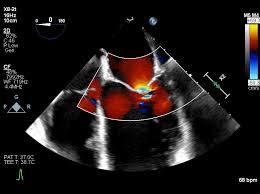

• اکوکاردیوگرافی (مهم‌ترین روش)

• اکو داپلر برای بررسی نارسایی میترال